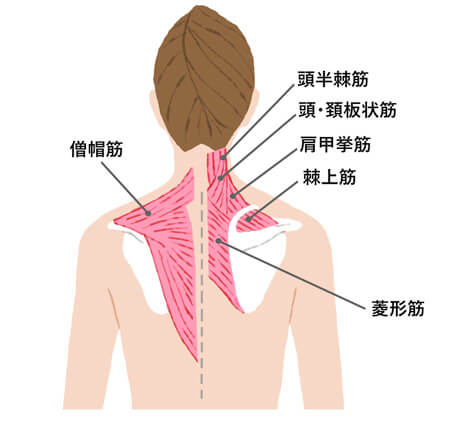

肩甲骨には、首や肩の動きに関係する多くの筋肉が付着しています。さらに、筋肉や靭帯といった組織を介して腕や鎖骨などと連結しているため、肩の運動に非常に重要な働きをしています。例えば、腕を上げる時は必ず肩甲骨が回旋します。そのため、肩甲骨の動きを止めてしまうと、腕を十分に上げることができません。肩や首のこり、痛みといった症状に、肩甲骨ならびに肩甲骨周辺の筋肉の働きが深く関わっています。

肩甲骨周囲の筋肉は色々ありますが、肩揉みなどでほぐせるのは体の表面にある筋肉です。例えば、肩には僧帽筋(そうぼうきん)と呼ばれる筋肉があります。体の表面にある筋肉のため、揉みほぐしやすい部分です。しかし、僧帽筋の奥にある菱形筋(りょうけいきん)や肩甲挙筋(けんこうきょきん)といった筋肉が肩こりに影響している場合は、体の奥に位置するため、揉むだけでは改善しません。